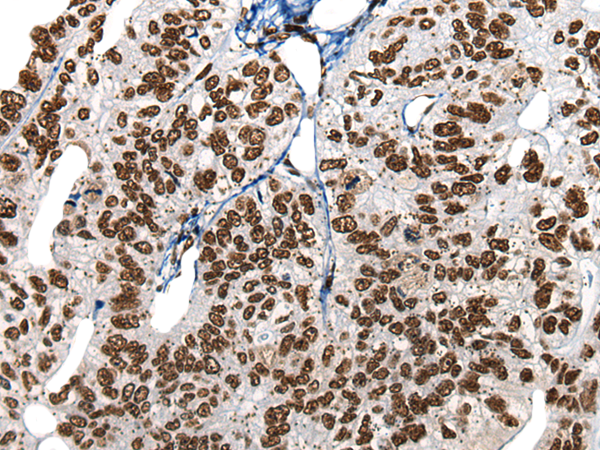

分类: 科研抗体货号: P13146别名: SCP; SPC; UCNIII应用: WB,IHC反应种属: Human